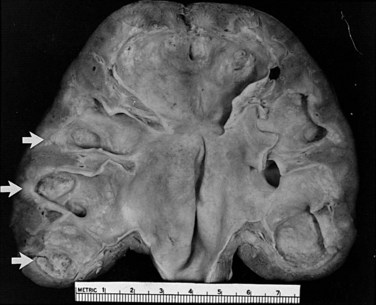

The opportunity for pathologic confirmation of acute bacterial nephritis is rare. The kidney may be edematous. Focal acute suppurative bacterial nephritis caused by hematogenous dissemination of bacteria to the renal cortex is characterized by multiple focal areas of suppuration on the surface of the kidney (Fig. 10–15). Histologic examination of the renal cortex shows focal suppurative destruction of glomeruli and tubules. Adjacent cortical structures and the medulla are not involved in the inflammatory reaction. Acute ascending pyelonephritis is characterized by linear bands of inflammation extending from the medulla to the renal capsule (Fig. 10–16). Histologic examination usually reveals a focal wedge-shaped area of acute interstitial inflammation with the apex of the wedge in the renal medulla. Polymorphonuclear leukocytes or a predominantly lymphocytic and plasma cell response are seen. Bacteria also may be present.

The changes that appear to be most specific for chronic pyelonephritis are evident on careful gross examination of the kidney and consist of a cortical scar associated with retraction of the corresponding renal papilla (Hodson, 1965a, 1965b; Heptinstall, 1974; Freedman, 1979). The kidney shows evidence of patchy involvement with numerous chronic inflammatory foci mainly confined to the cortex but also involving the medulla (Fig. 10–17).

Figure 10–17 Chronic pyelonephritis. The renal cortex shows thickened fibrous capsule and focal retracted scar on surface of kidney. Focal destruction of tubules in center of picture is accompanied by periglomerular fibrosis and scarring.

(From Schaeffer AJ. Urinary tract infections. In: Gillenwater JY et al, editors. Adult and pediatric urology. Philadelphia: Lippincott Williams & Wilkins; 2002. p. 211–72.)

The scars may be separated by intervening zones of normal parenchyma, causing a grossly irregular renal outline. The microscopic appearance, as with most chronic interstitial disease, includes the presence of lymphocytes and plasma cells. Although glomeruli within scars may be surrounded by a cuff of fibrosis or be partially or completely hyalinized, glomeruli outside these severely scarred zones are relatively normal. Vascular involvement is variable, but in patients with hypertension, nephrosclerosis may be found. Papillary abnormalities include deformity, sclerosis, and sometimes necrosis. Studies in animals have clearly indicated the critical role of the papilla in the initiation of pyelonephritis (Freedman and Beeson, 1958). However, these changes are not necessarily specific for bacterial infection and may occur in the absence of infection as a result of other disorders such as analgesic abuse, diabetes, and sickle cell disease.